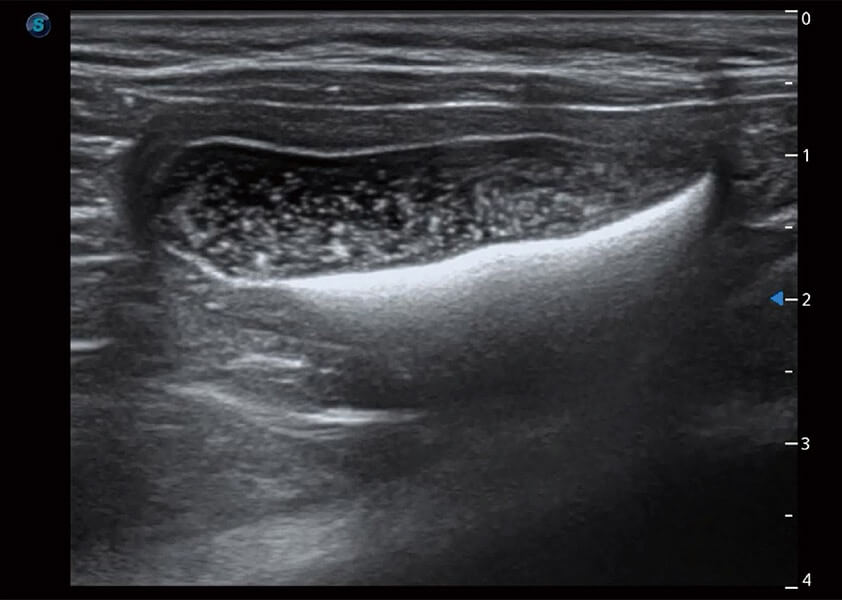

ProPet 60 作为一款高端台式动物超声设备,为动物医生的日常诊断提供了一系列贴合动物临床需求、解决临床实际问题的高级成像功能。凭借全系列高清探头,满足医生对腹部、心脏、生殖、浅表、肌骨等成像的所有需求,切实帮助您提升检查效率,提高诊断信心。

动物是人类最亲密的朋友和最值得信赖的伙伴。美狮贵宾会官网也一直致力于探索动物专用的超声影像解决方案。 全新推出的ProPet系列,是美狮贵宾会官网在动物超声影像智能化、专业化、精准化的一次跨越式革新。动物不能用言语来表述自己的不适,通过超声影像,ProPet系列搭建了动物医生与不同物种沟通的“桥梁”,为动物医生注入了“治愈之力”。